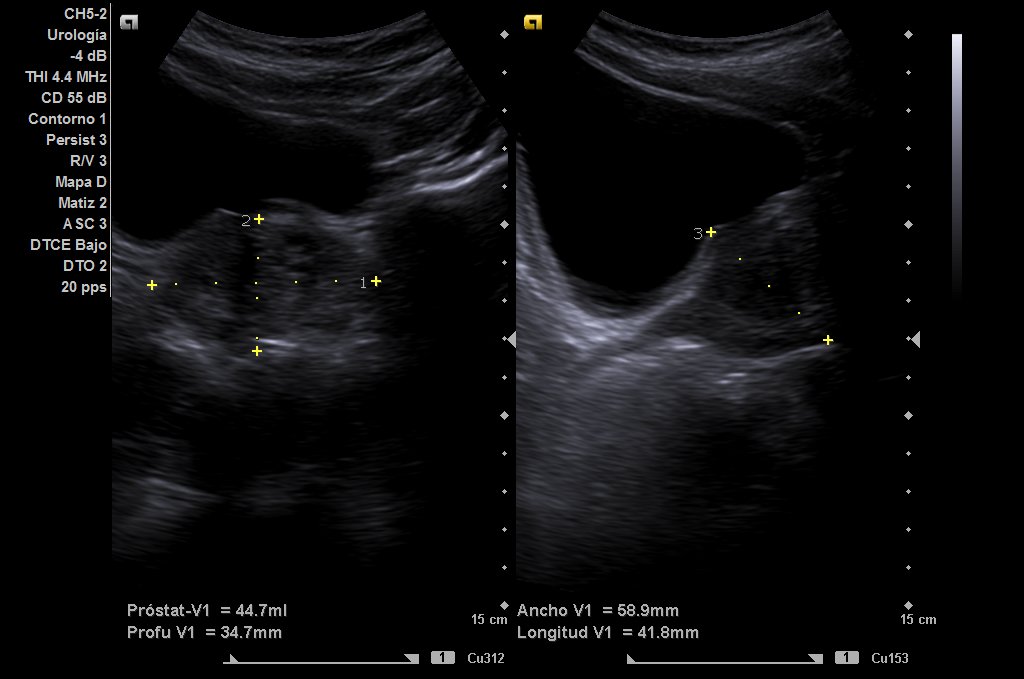

Paciente de 56 años, diagnosticado de enfermedad renal crónica estadío G3A A1 de origen no filiado, que en analítica de control presenta PSA 6,79, por lo que se decide realizar ecografía abdomino-pélvica para medición de volumen prostático.

Riñones de tamaño y ecoestructura normales, con buena diferenciación parénquima-seno en polo inferior de riñón derecho, quiste simple de aproximadamente 6 centímetros de eje mayor (ya conocido) y en riñón izquierdo, quiste cortico-sinusal de menos de 2 cm (también conocido). Próstata de 44 gramos. En hipocondrio izquierdo observamos imagen redondeada con contenido ecogénico, con tractos hiperecogénicos en su interior que podría corresponderse a dilatación ángulo esplénico de colon.

Analítica con PSA 7’71, PSA libre/total 23%.